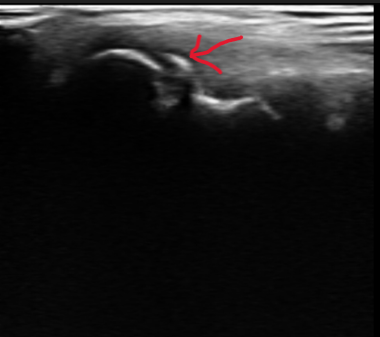

エコー画像では、上腕骨小頭という丸みのある骨(エコー画像 赤丸部)が正常な場合は、滑らかな半円を描きますが、野球肘側の画像はギザギザしているのが確認できます。

野球肘の診察においてエコー検査は欠かせません。野球肘検診などもエコーが大活躍しています。